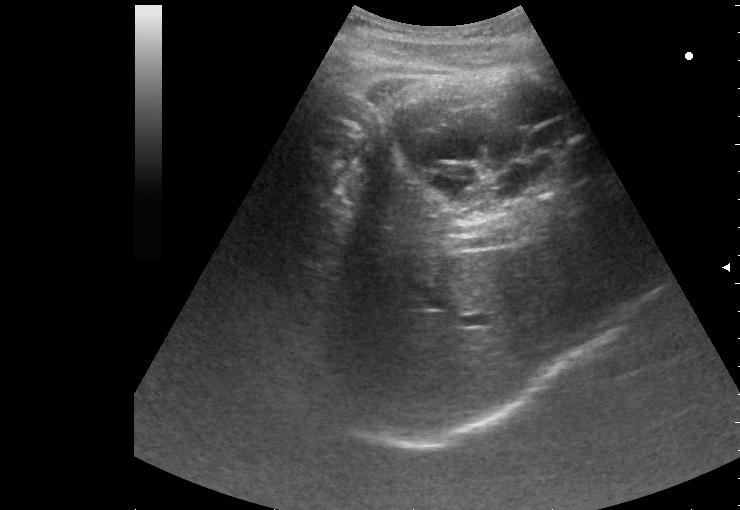

17-летняя девушка с множественными поражениями печени

спустя 8 мес. после операции